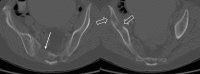

Annotated contrast-enhanced chest CT with coronal reconstruction in bone windows (A) and axial reconstruction in soft tissue windows (B) show an expansile destructive lytic lesion centred in the posterior right fourth rib, involving the T3 and T4 vertebral bodies, with a soft tissue component extending into the T3–T4 neural foramen (arrow).